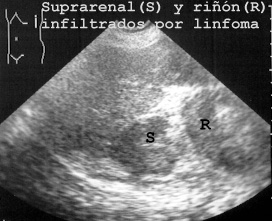

Pero así como en los niños las suprarrenales son muy fáciles de observar, en los adultos sólo las vemos cuando están aumentadas de tamaño como ocurría en la Fig 48 debido a infiltración por un linfoma.